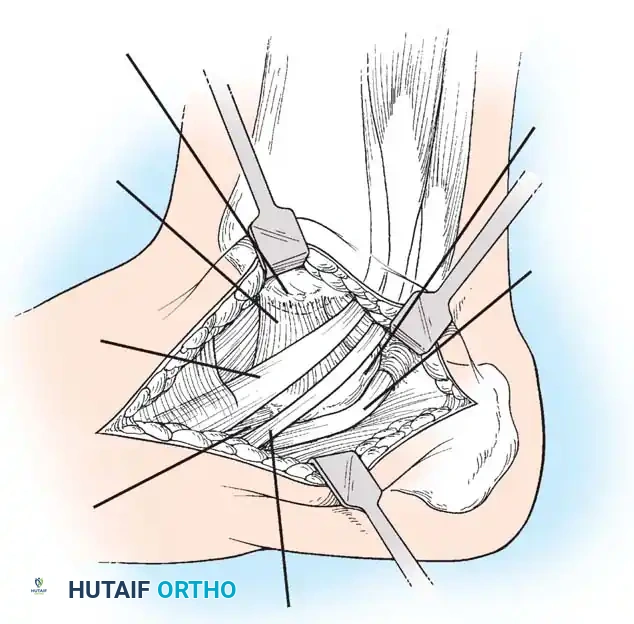

جراحة إزالة التحام العقب والزورقي

في حالة التحام العقب والزورقي، يعتبر الاستئصال الجراحي للجسر العظمي هو الخيار المفضل، خاصة لدى الأطفال والمراهقين الذين لا يعانون من خشونة في المفاصل.

يقوم الجراح بإزالة الجسر العظمي بالكامل لضمان عدم عودته. ولمنع تكوّن العظم مرة أخرى في نفس المكان، يتم وضع نسيج عازل في الفراغ الناتج، مثل جزء من عضلة مجاورة (Extensor digitorum brevis) أو نسيج دهني، أو استخدام الشمع الطبي. أثبتت الدراسات أن هذه الجراحة تنجح بنسبة عالية في تخفيف الألم واستعادة جزء كبير من حركة المفصل.